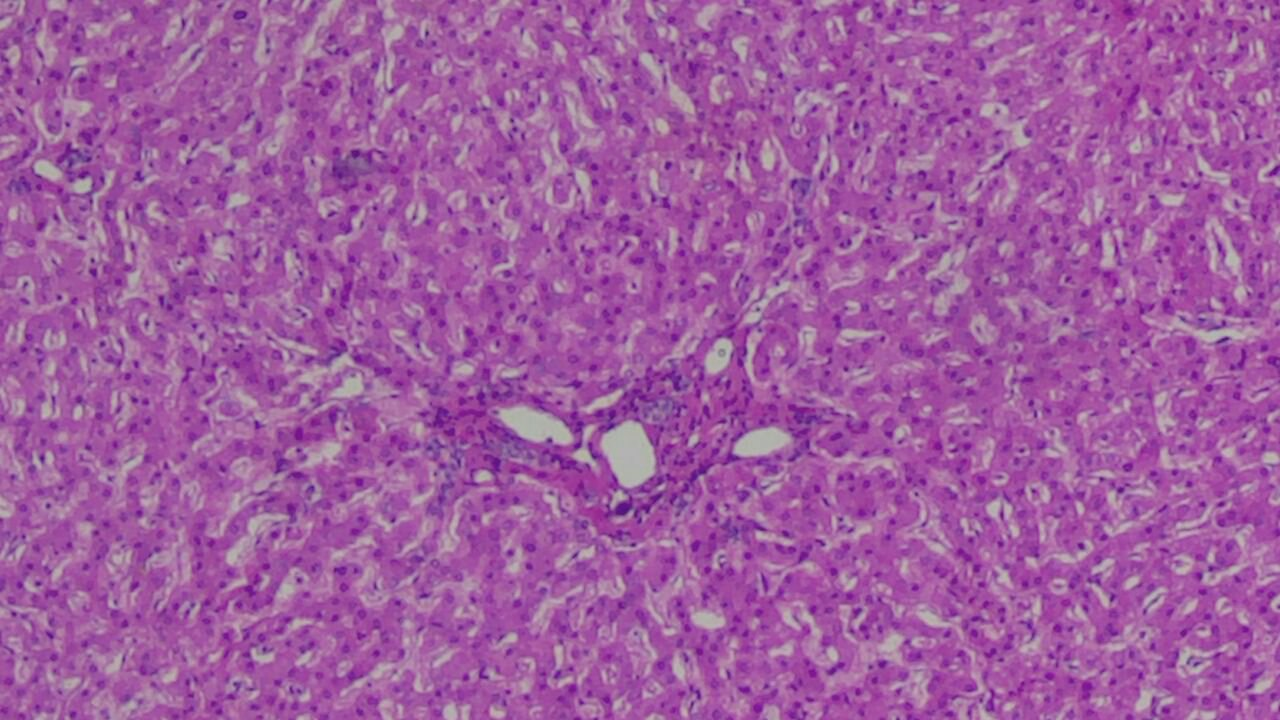

The majority of those who died from acute poisoning exhibited severe disturbances in acid-base balance, primarily metabolic acidosis (81.6%), reflecting the severity of hypoxic and toxic tissue damage. A significant frequency of dyselectrolytemia (71.1%) and cytolytic syndrome (76.3%) indicates systemic damage to cell membranes and enzyme systems. Signs of acute renal failure were recorded in 63.2% of cases.Histopathological Analysis of the Myocardium. In the examined histological preparations, the myocardium is represented by bundles of cardiomyocytes arranged unevenly, with pronounced signs of acute toxic-hypoxic damage. The architecture of the muscle fibers is disrupted. Cardiomyocytes in some areas are sharply eosinophilic, with a loss of normal transverse striation. Fragmentation and wavy deformation of muscle fibers are observed, as well as foci of dissociation with widening of the intermuscular spaces. In some areas, contracture changes in cardiomyocytes with densification of the sarcoplasm are identified, which is considered an early morphological sign of acute myocardial damage. The nuclei of cardiomyocytes are heterogeneous: some are hyperchromic and elongated, while others exhibit karyopyknosis or karyolysis. Vacuolization of the sarcoplasm is noted in several cardiomyocytes, reflecting metabolic dystrophy. The stroma of the myocardium is edematous, and intermuscular spaces are expanded. Capillaries and venules are sharply congested, occasionally showing signs of stasis. Diapedetic hemorrhages are determined in individual fields of vision. An inflammatory cellular reaction is absent, which corresponds to an acute, necrotic-dystrophic process of non-infectious genesis (Fig. 1). | Figure 1. Myocardium represented by bundles of cardiomyocytes arranged unevenly, with pronounced signs of acute toxic-hypoxic damage. Stained with H&E, mag. 10x20 |

The architecture of the muscle fibers is disrupted. Cardiomyocytes in some areas are sharply eosinophilic, with a loss of normal transverse striation. Fragmentation and wavy deformation of muscle fibers are observed. The nuclei of cardiomyocytes are heterogeneous: some are hyperchromic and elongated, while others exhibit karyopyknosis, and in some places, karyolysis. Morphological Findings in Other Organs. Morphological examination of the corpses of individuals who died from acute oral poisoning revealed a complex of typical histological changes, indicating systemic toxic damage to the body and the development of severe hypoxic-metabolic disorders. Brain: In all observations, signs of pronounced cerebral edema, expansion of perivascular spaces, venous congestion, and focal perivascular hemorrhages were noted. These findings reflect impaired microcirculation and hypoxic damage to the nervous tissue. Liver: Dystrophic changes in hepatocytes predominated, with the development of fatty degeneration (steatosis) of varying degrees of severity. In the central zones of the hepatic lobules, areas of centrilobular necrosis were identified, indicating the high sensitivity of hepatocytes to toxic effects and ischemia. | Figure 2. Hepatocytes are predominantly enlarged, with pale, granular cytoplasm showing pronounced signs of acute toxic dystrophy. Stained with H&E, mag. 10x20 |